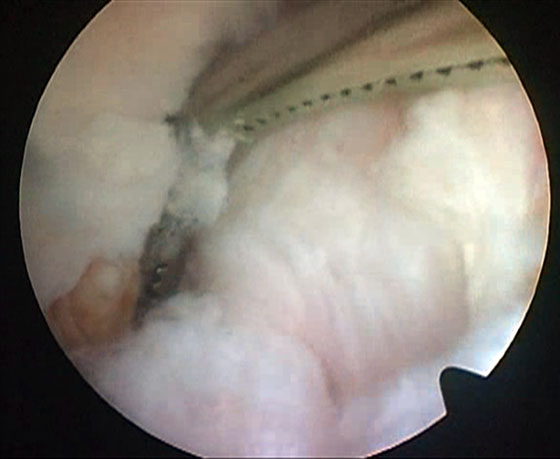

Se insufla el manguito neumático y se comienza la artroscopia por los portales anteromedial y anterolateral, se reconoce la lesión, se solucionan lesiones asociadas (meniscales, condrales, cuerpos libres) y se pasa a realizar el túnel femoral. Se localiza la hora 12 del intercóndilo, se visualiza la tróclea femoral y se ubica el sitio del túnel femoral (hora 1 rodilla derecha, hora 11 rodilla izquierda) (Fig. 2). Este túnel debe estar lo más alto posible en el intercondilo para colocar un injerto bien “vertical”. Realizamos este paso primero, haciendo el túnel desde el portal anterolateral, para evitar la dificultad de realizarlo después de la liberación capsular posterior que nos dejará menor cantidad de líquido intraarticular, y consecuentemente menor distensión dificultando la visión. Identificado el sitio de inserción, y sin resecar las fibras remanentes se coloca la fresa del diámetro a utilizar de manera de buscar que queden unos 3 mm desde la parte periférica proximal de la fresa hasta el cartílago articular del fémur, se pasa a través de la fresa canulada un clavo guía, se retira la fresa para confirmar la ubicación y se realiza el túnel de 20 o 25 mm de largo, de acuerdo al tipo de injerto que utilicemos. A continuación se ubica el espacio entre las fibras remanentes del LCP y el LCA, se debrida con shaver para dejar permeable este espacio, que nos permitirá más tarde traer el injerto desde la inserción tibial hacia la parte anterior de la rodilla (Fig. 3).

Figura 3